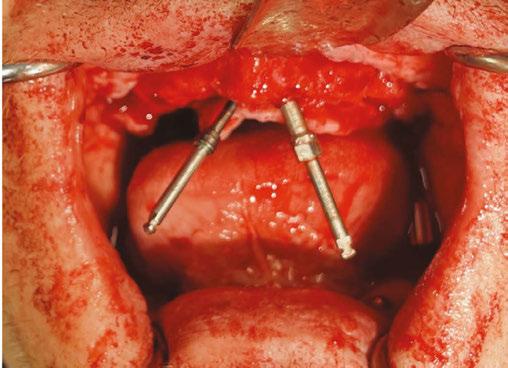

Following PATZi, anterior support was sought next. As such, the nasal mucosa was elevated to expose the floor of the nasal cavity and the bone of the inferior conchae. A pair of 25 mm transnasal implants were placed, and each achieved high insertion torque of 45+ Ncm (Figures 9-11). Continuing with the PATZi protocol and treatment plan, 42.5 mm long zygomatic implants were placed in both zygomas. The zygomatic implants were placed using an extrasinus approach and both achieved insertion torque of 45+Ncm. Buccal fat pedicles were advanced bilaterally to cover extrasinus portions of the zygomatic implants, and flap closure was achieved with 4-0 chromic gut suture. The patient was immediately temporized with a screw-retained transitional bridge (Figure 12), and a final zirconia restoration was delivered after 8 months of healing (Figure 13).

3 (left): 3-dimensional CBCT rendering of patient treated with transnasal dental implants as an alternative to quad-zygomatic implant treatment. Figure 4 (right): Intrasurgical photo of transnasal dental implant traversing the nasal cavity and engaging the base of the inferior concha